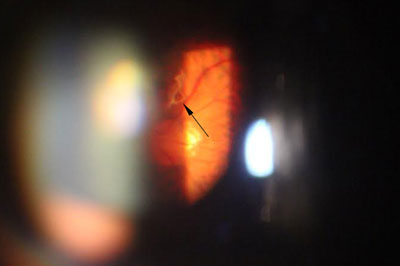

「飛蚊」是一種很常見的視覺障礙,一般是形容視覺上出現可跟隨眼睛移動而浮游的暗黑障礙物,形狀可呈點狀,線狀,網形,孤形或環形。嚴格來說,「飛蚊症」並不是一種眼疾,而是一種視覺上的不適症狀。成因大部份是由於眼內呈啫喱狀的玻璃體,出現液化,而形成各種形狀和大小不一的「殘留物」。「飛蚊症」其他成因亦可以是由於玻璃體出現出血或發炎等病變而導致。常見玻璃體出血的原因包括視網膜撕裂,視網膜脫落和糖尿上眼等等。所以如患深近視,糖尿病患者或出現突發性嚴重飛蚊症狀,應盡快求醫,作出詳細眼睛檢查。

年屆四十至五十歲的病人,出現急症飛蚊大多是由於玻璃體液化以至出現「後玻璃體脫落」,當玻璃體從視神經盤脫離時,往往便出現較大和明顯的玻璃體「殘留物」,而導致嚴重飛蚊症狀,小部份病人亦會出現視網膜裂痕,出血和脫落等併發症,以致危害視力。雖然大部份病人沒有視力嚴重受損的風險,但較嚴重的飛蚊症狀會帶來視覺上的不便。治療此類飛蚊症,一般藥物治療效果有限,而侵入性外科手術 (玻璃體切除) 亦只適合如玻璃體出現嚴重出血或撕裂等併發症患者。